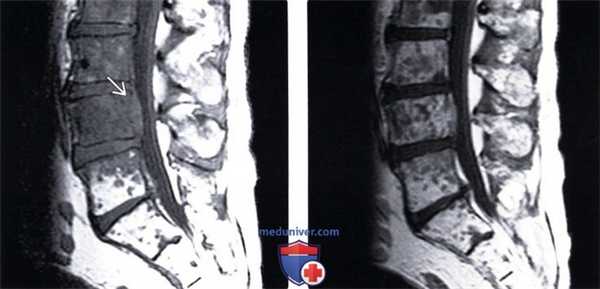

(Слева) Сагиттальный срез, Т1-ВИ, пациент с раком легкого: после проведенной лучевой терапии отмечается рецидив опухолевого роста. На уровне L2-L5 отмечается диффузное снижение интенсивности сигнала, на уровне L4-эпидуральное распространение опухоли.

(Справа) Сагиттальный срез, Т1-ВИ с КУ: множественные низкоинтенсивные метастатические очаги поражения, которые на фоне введения контраста становятся менее заметными вследствие диффузного усиления сигнала опухолью и приближения его интенсивности к сигналу жирового костного мозга.